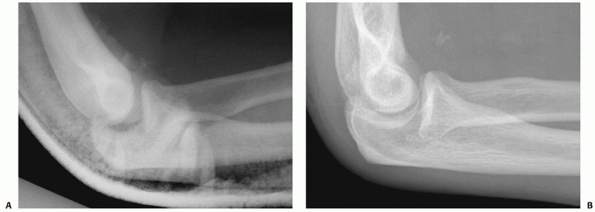

FIGURE 32-18 Small coronoid fractures are often problematic. A. This appears to be a small isolated fracture of the coronoid. B.

On the anteroposterior view, it is clear that the anteromedial facet of the coronoid process is fractured. There is varus subluxation and opening of the joint on the lateral side betraying the associated lateral collateral ligament injury. C. Three-dimensional computed tomography depicts external rotation of the distal humerus with respect to the forearm as the trochlea rotates forward into the coronoid defect. D. There are separate coronoid tip and anteromedial facet fracture fragments. (continues) |

FIGURE 32-18 (Continued) E.

Exposure is obtained by transposing the ulnar nerve anteriorly and elevating the anterior portion of the flexor-pronator muscles off of the medial collateral ligament and the coronoid process. F. The coronoid fractures were secured with a buttress plate and the lateral collateral ligament origin was reattached to the lateral epicondyle with a suture anchor. G. A concentric reduction and good elbow function resulted. |

anteromedial facet of the coronoid preferentially. (ii) Varus

fracture of the anteromedial facet of the coronoid process (Fig. 32-18).